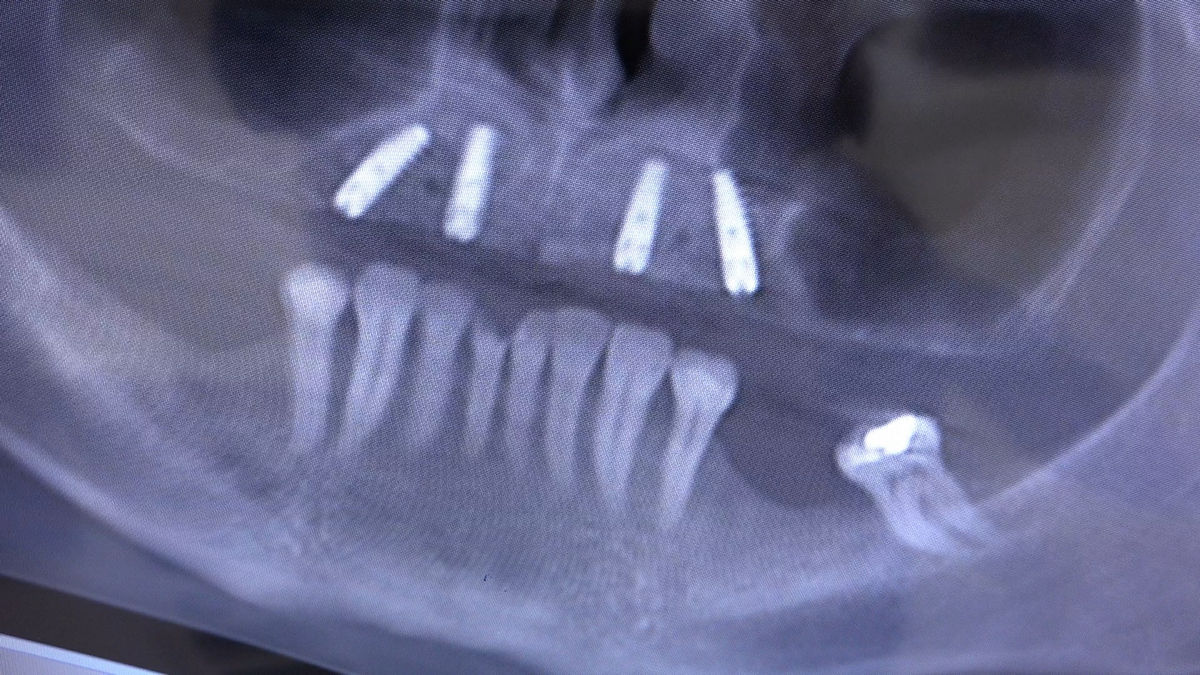

Chirurgia implantologiczna to temat wiodący 5 Sesji X Sezonu Practiculum Implantologii, która się odbyła 23-24 października 2020 roku. Bierze w nim udział 16 adeptów implantologii stomatologicznej. Zabiegi z udziałem Pacjentów jak zwykle poprzedziło omówienie i planowanie, tym bardziej, że zgodnie z planem wykonana została implantacja z wykorzystaniem szablonu chirurgicznego, który przygotowało laboratorium dentystyczne Wiligała Lab. Kursanci wykonywali szereg zabiegów implantologicznych i chirurgicznych oraz regeneracyjnych z zastosowaniem PRF, w tym sinus lift. Przeprowadzali je pod kierunkiem Lidera Umiejętności Implantologicznych dr n.med. Violetty Szycik, która wysoko oceniła wykonanie zabiegów.